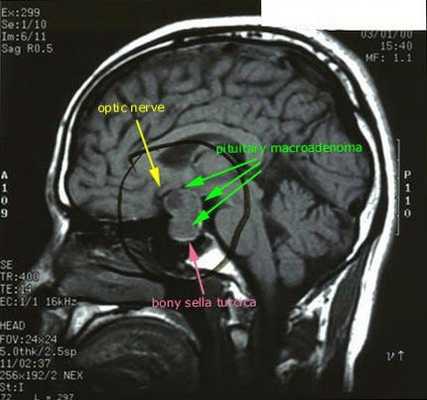

Синдром Иценко-Кушинга – широкое понятие, включающее комплекс различных состояний, характеризующихся гиперкортицизмом. Согласно современным исследования в области эндокринологии более 80% случаев развития синдрома Иценко-Кушинга связано с повышенной секрецией АКТГ микроаденомой гипофиза (болезнь Иценко-Кушинга). Микроаденома гипофиза представляет небольшую (не более 2 см), чаще доброкачественную, железистую опухоль, продуцирующую адренокортикотропный гормон.

В моче повышено содержание 11-ОКС (11-оксикетостероидов) и снижено 17-КС. В крови гипокалиемия, увеличение количества гемоглобина, эритроцитов и холестерина. Для определения источника гиперкортицизма (двусторонняя гиперплазия надпочечников, аденома гипофиза, кортикостерома) проводится МРТ или КТ надпочечников и гипофиза, сцинтиграфия надпочечников. С целью диагностики осложнений синдрома Иценко-Кушинга (остеопороза, компрессионных переломов позвонков, перелома ребер и т. д.) проводится рентгенография и КТ позвоночника, грудной клетки. Биохимическое исследование показателей крови диагностирует электролитные нарушения, стероидный сахарный диабет и др.

После подтверждённого гиперкортицизма необходимо проведение инструментальных методов исследования (МРТ гипофиза, КТ надпочечников).

При БИК в 80-85% случаев выявляют микроаденому гипофиза (опухоль до 10 мм), у остальных 15-20% — макроаденому (доброкачественное новообразование от 10 мм). [7]